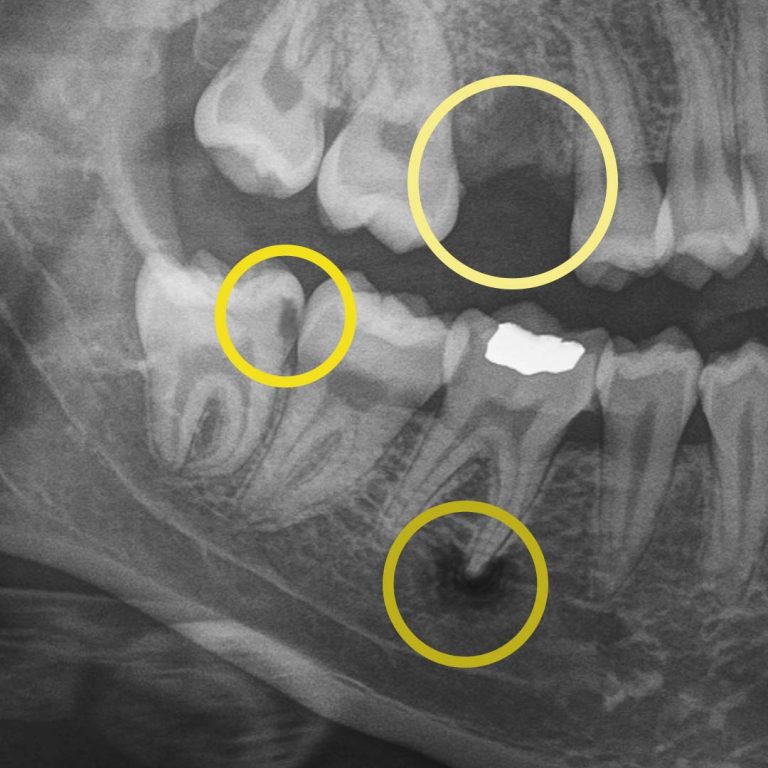

Digital X-rays allow us to look beyond what’s visible. They help us detect:

• cavities between teeth.

• early decay hiding under fillings or crowns.

• bone changes related to gum disease.

• infections at the root of a tooth.

• subtle cracks.

For example, during a routine digital X-ray, we may notice a small shadow between two teeth. To the naked eye, everything can look healthy, but that faint shadow often tells us the enamel in that area is starting to weaken. This is considered early-stage tooth decay, sometimes called early “caries.”

Before this decay turns into a hole in the tooth, also known as a “cavity,” we can begin proactive treatment that can prevent the decay from worsening. A prescribed treatment like Curodont™ can repair the tooth (without drilling!) by helping guide minerals back into the enamel and supporting the tooth’s natural ability to heal when it’s paired with good brushing, flossing, and regular professional care. This approach allows us to be non-invasive and protect your natural tooth.

At your next X-ray visit, we’ll compare images to see whether that spot has stabilized or improved. If the area worsens and the enamel breaks down further, a small dental filling may be necessary to prevent deeper decay damaging the tooth structure. If the decay continues unchecked and reaches the inner portion of the tooth where the nerve lives, treatment becomes more complex, often requiring root canal therapy, which can be time-consuming, uncomfortable, and costly.